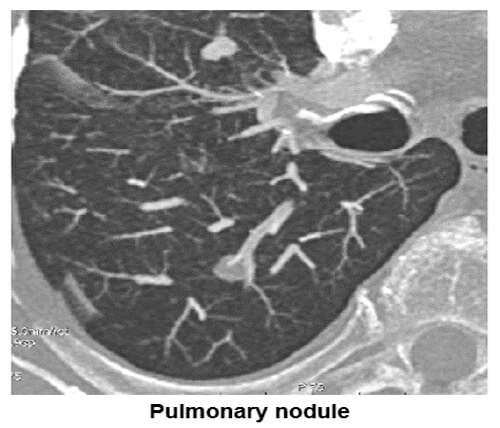

Pulmonary Nodules

The image shows where the maximum intensity projection is used to search for parenchyma solid nodular lesions. Notice the pulmonary lesion in the lung field.